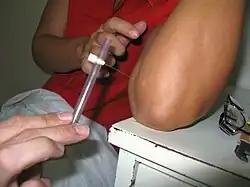

The Bacillus Calmette–Guérin (BCG) vaccine offers a variable amount of protection against leprosy in addition to its closely related target of tuberculosis.[78] It appears to be 26% to 41% effective (based on controlled trials) and about 60% effective based on observational studies, with two doses possibly working better than one.[79][80] The WHO concluded in 2018 that the BCG vaccine at birth reduces leprosy risk and is recommended in countries with high incidence of TB and people who have leprosy.[81] People living in the same home as a person with leprosy are suggested to take a BCG booster which may improve their immunity by 56%.[82][83] Development of a more effective vaccine is ongoing.[14][84][85][86]

A novel vaccine called LepVax entered clinical trials in 2017 with the first encouraging results reported on 24 participants published in 2020.[87][88] If successful, this would be the first leprosy-specific vaccine available.